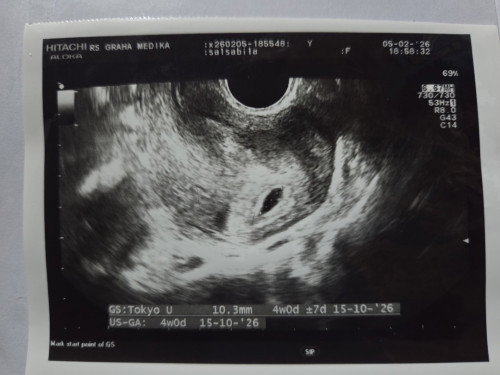

Pertama kali usg week 4 ya memang kantong kehamilan aja kedeteksi nya soalnya aku gatau hehe ,terus disuruh balik lagi week 8 (5 maret ini moms)apakah detak jantung janin nya sudah kedeteksi? mending aku dtg 5 maret pas 8week atau nunggu dulu yaa sebaiknya kapan?Apa aja pertanyaan ke dokter nya nanti soalnya dokternya kureng informatif mungkin ada rekomendasi dr di RS graha medika Gambiran atau sekitarnya kemarin sama Bu made terimakasih banyak maaf new mom sharing dong#Sharingdong_Bund #Needadvice #mohonbantujawabbunda #firstmom